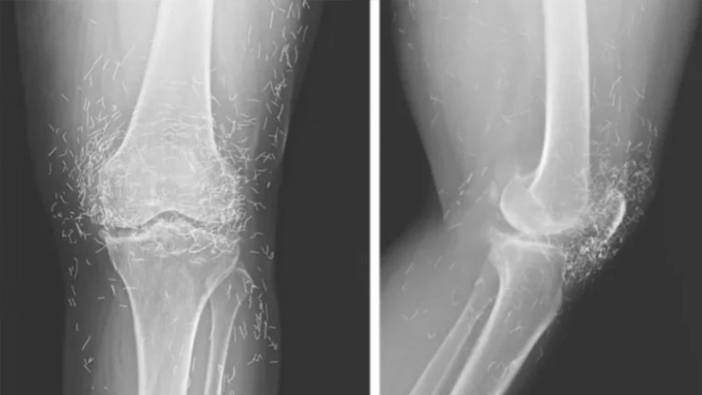

Hastanede yapılan tetkikler sonucunda, röntgendeki altın ipliklerin, kadının düzenli olarak uygulattığı altın iplik akupunkturu seanslarında bilerek bırakıldığı öğrenildi. Bu uygulamada steril kısa altın iplikler dokuya yerleştirilerek sürekli uyarım sağlanması amaçlanıyor.

Ayrıca bu ipliklerin görüntüleme teknikleri üzerinde de olumsuz etkileri olabiliyor. Röntgenlerde yorumlamayı zorlaştırmasının yanı sıra, manyetik rezonans (MR) görüntülemelerinde ipliklerin hareket etmesi ve damarlara zarar vermesi riski bulunduğu vurgulandı.

Doktorlar, bu tür geleneksel tedavi yöntemlerine başvuran hastalarda altın ipliklerin varlığının mutlaka göz önünde bulundurulması gerektiğini belirtiyor. Neyse ki ipliklerin röntgende rahatça görülebilmesi sayesinde konumları zamanla takip edilebiliyor.